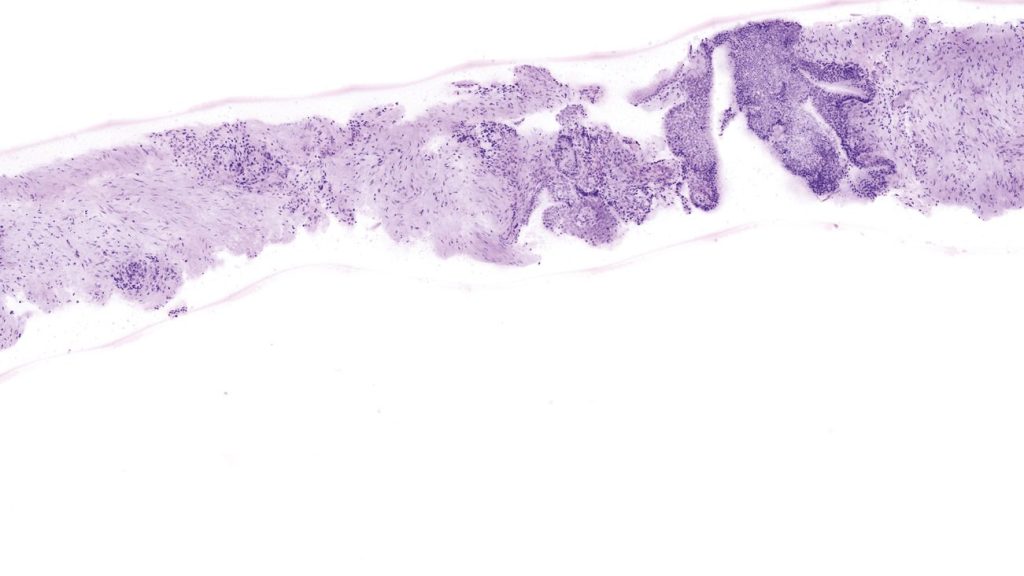

VivaScope GmbH is known for its state-of-the-art non-invasive skin diagnostic devices that help doctors and dermatologists around the world to make accurate diagnoses and provide their patients with the best possible treatment. Through continuous research and development, the company has constantly improved its products and set new standards in the industry.